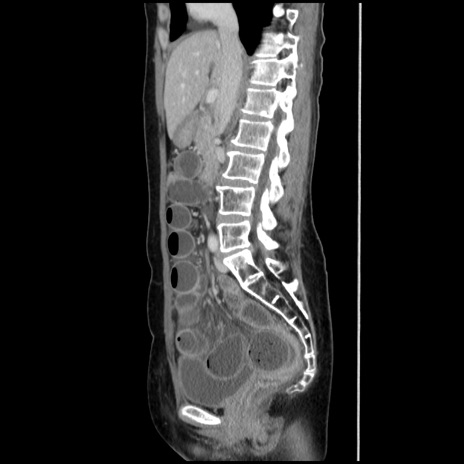

症例32(矢状断像)

【症例】40歳代 女性

【主訴】上腹部痛、嘔気・嘔吐

【現病歴】約9時間前頃から急に上腹部痛、嘔気、嘔吐が出現。改善しないため救急要請。

【既往歴】子宮頚癌(広汎子宮全摘術、放射線療法)、腸閉塞

【身体所見】腹部:平坦、軟、腸雑音亢進、上腹部を中心に腹部全体に圧痛あり。

【データ】WBC 8400、CRP 0.03